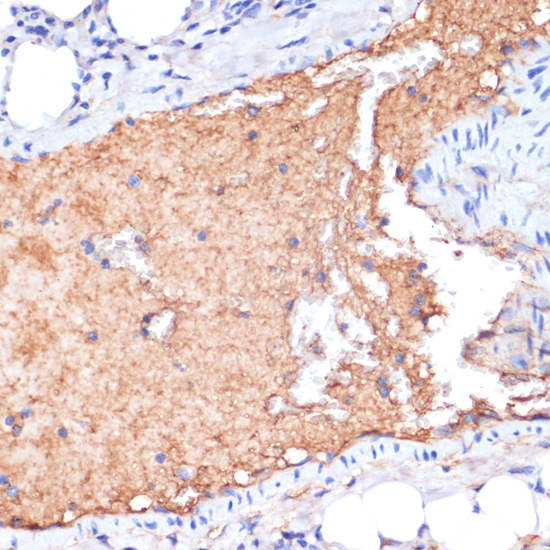

Immunohistochemistry of paraffin-embedded mouse liver using APOA1 at dilution of 1:100 (40x lens).

Immunohistochemistry of paraffin-embedded mouse lung using APOA1 at dilution of 1:100 (40x lens).

Immunohistochemistry of paraffin-embedded mouse brain using APOA1 at dilution of 1:100 (40x lens).